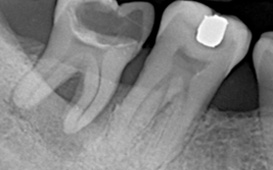

| X光檢查 | 硬組織型態 |

牙周組織破壞包括 :

骨頭吸收、牙齦發炎、牙齒動搖